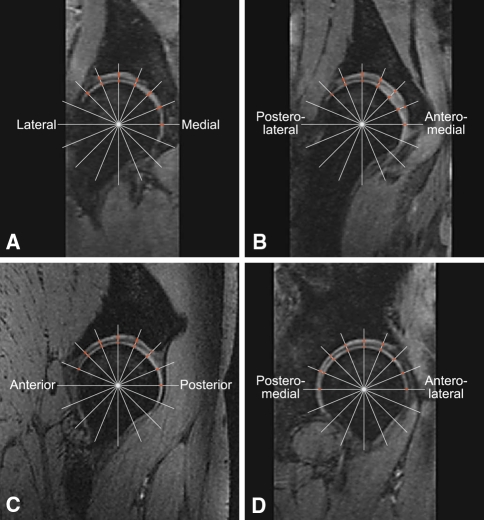

To measure the thickness of the acetabular and femoral cartilage, we used our earlier developed stereologic method that is reliable and time-efficient (requiring approximately 20 minutes per hip) [21, 22]. Stereologic methods are used to obtain quantitative information regarding 3-D structures based on observations from section planes or projections [33]. Stereology can be used to minimize the workload using sampling and still provide reliable quantitative information about the whole structure of interest. This method is based on four images through the center of the femoral head: a true coronal, a true sagittal, an oblique coronal 45° forward angled, and an oblique coronal 45° backward angled. On each of the four images, a grid of 15 to 20 radial test lines was selected and located randomly on the images and where the test lines intercepted the cartilage, the orthogonal distance through the cartilage was measured manually in software (Grain 32, Dimac, and KT Algorithms, Aarhus, Denmark) designed for stereologic purposes (Fig. 1). The approximately 60 to 80 measured distances were summed and the mean thickness of the acetabular and femoral cartilage, respectively, was calculated. Systematic uniformly random sampling ensured the location of the test lines intercepting the cartilage was sampled with the same probability. Therefore, we did not need to use anatomic landmarks to compare preoperative and postoperative cartilage thickness. One observer (IM) measured cartilage thickness on all images. The contrast of the MR images was not adjusted before or during measuring because this may change the appearance of the cartilage boundaries and thus affect the thickness measurements. The cartilage measures were not affected by partial volume because we used center MR images (through the center of the femoral head). It was not difficult to differentiate the labrum from the cartilage on the images. As noted previously, 18 of the 26 patients agreed to undergo MRA 3½ years after PAO to investigate if they had an acetabular labral tear. Applying standardized aseptic technique and guided by fluoroscopy, 8 mL of diluted gadolinium contrast media (Gd-DTPA 2 mmol/L; Magnevist, Schering, Berlin, Germany) was injected into the hip through an anterior approach. Before injection, the intraarticular position of the needle point was verified by injecting a few drops of iodinated contrast media. There were no adverse affects. MRA was performed using the same 1.5-T scanner as used for MRI in this study. Initially, three scout sequences in the axial, sagittal, and coronal planes were obtained. This was followed by T1-weighted sequences with fat suppression: true coronal, oblique axial (parallel to the femoral neck), oblique coronal 45° forward angled, and oblique coronal 45° backward angled (TR/TE 376/20, slice thickness 4 mm, field of view 220 × 220, matrix 256 × 256). Finally, a coronal STIR sequence through the entire pelvis was performed (TR/TE 410/27, TI 170, field of view 400 × 400, matrix 256 × 256). MRA and intraarticular contrast injections were performed by a senior radiologist (JG) specialized in musculoskeletal MRI. All images were assessed by masked rereadings separated by 4 weeks and it was noted where the labral tears were located on the acetabular rim (Fig. 2). The criteria for labral tears seen with MRA were (1) displacement or (2) absence of the labrum; (3) contrast media through the base of the labrum causing detachment with or without displacement; and intrasubstance (4) linear; (5) cystic; or (6) irregular presence of contrast media. Intermediate signal intensity and irregular margins were interpreted as degenerative changes [41].

Fig. 1A–B.

On each of four reconstructed MR images, (A) lateral-medial, (B) posterolateral-anteromedial, (C) anteroposterior, and (D) posteromedial-anterolateral, a grid of 15 to 20 radial test lines was superimposed, and where the test lines intercepted the cartilage, the orthogonal distance through the cartilage was measured manually. The approximately 60 to 80 measured distances were summed, and the mean thickness of the acetabular and femoral cartilage was calculated.